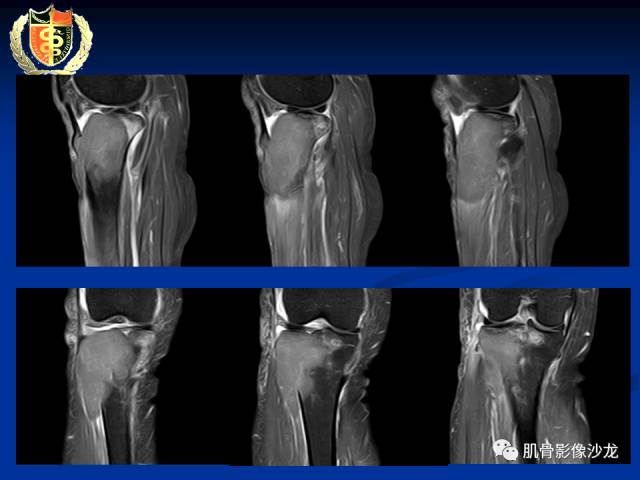

骨淋巴瘤及软骨肉瘤两例CT及MR影像表现

有症状,有骨膜反应,还是考虑肉瘤比较合适

目前看考虑软骨来源是合理的

这些应该是钙化吧

里面的高信号是软骨吧